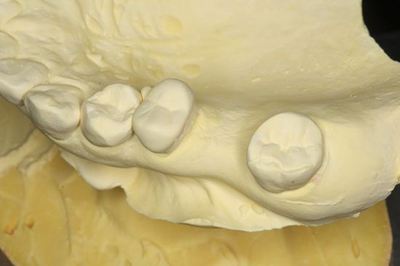

CTデータと重ね合わせて予定位置・方向に金属棒を植えます。

![]()

上下の歯の位置関係も確認します。

プラスチックでドリルガイドを作製します。(ライブピンクのレジンに意味はありません)